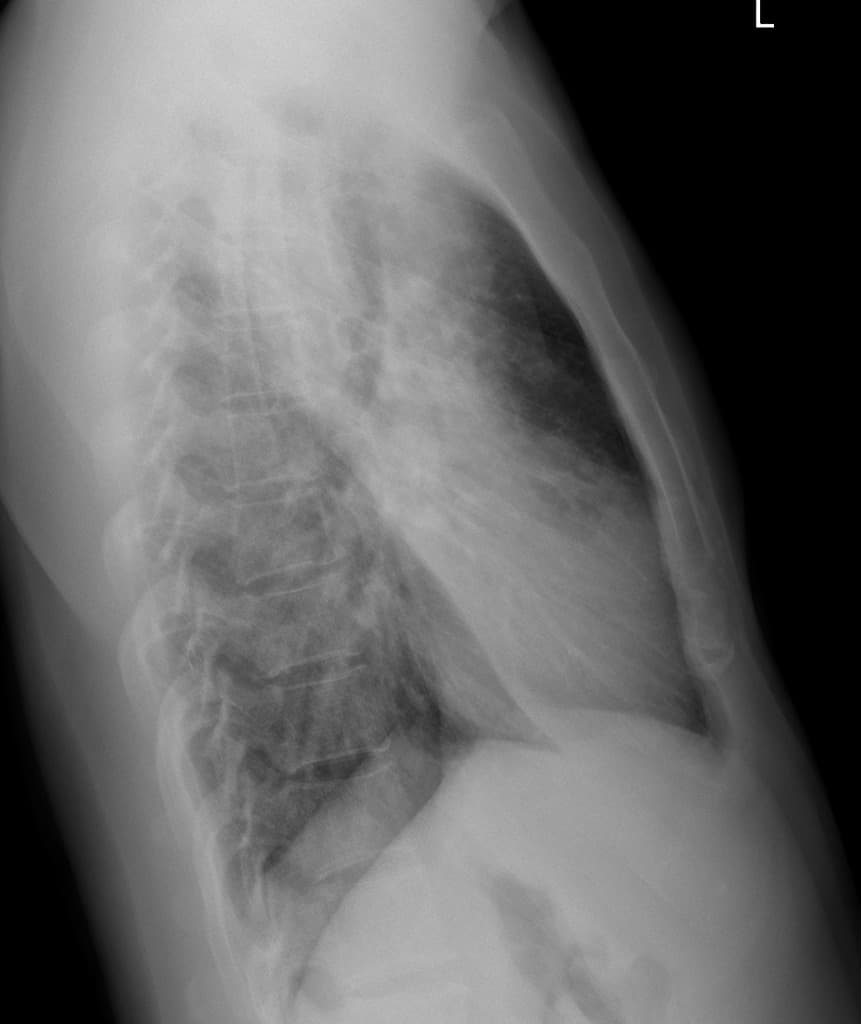

Lateral

Đau tức ngực và sụt cân. Bệnh nhân suy giảm miễn dịch với tiền sử bệnh lý lympho tổ chức bào nuốt hồng cầu (hemophagocytic lymphohistiocytosis).

Các nốt nhỏ lan tỏa rộng rãi ở phổi. Không thấy tổn thương xương đáng nghi ngờ.

Các nốt phổi nhỏ hai bên lan tỏa, kèm theo các vùng mờ đậm đặc khoảng kẽ và khoảng kẽ phế nang (chủ yếu ở thuỳ giữa phổi phải).

Tổng thể hình ảnh phù hợp với nhiễm trùng lan tỏa dạng lao kê (miliary infection – tuberculosis), chẩn đoán phân biệt bao gồm di căn (metastases).

Một trường hợp lao kê (miliary tuberculosis) với các dấu hiệu hình ảnh gợi ý bệnh lý lympho tổ chức bào nuốt hồng cầu (hemophagocytic lymphohistiocytosis).

Lao kê (miliary tuberculosis) và bệnh lý lympho tổ chức bào nuốt hồng cầu (hemophagocytic lymphohistiocytosis)